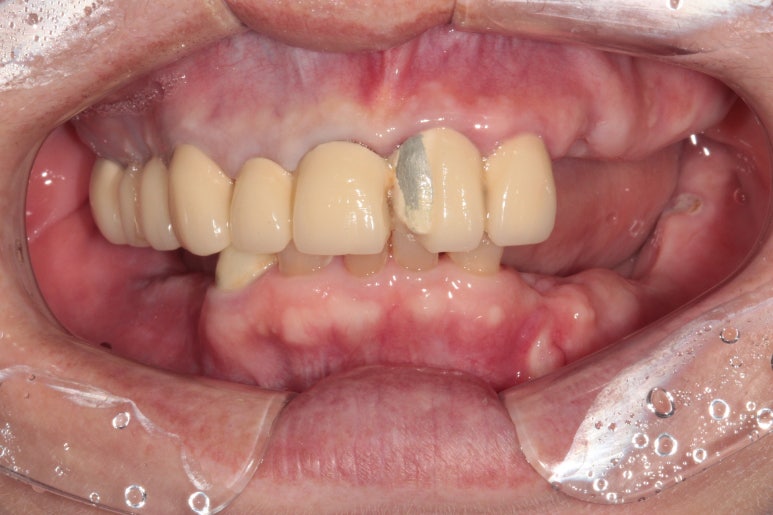

전체적으로 어금니가 여러개 없어요. 앞니는 깨졌어요.

처음 오셨을 때 촬영한 정면 구강 내 사진입니다.

위 앞니 보철물은 도재 (포세린,porcelain)가 깨져있어 보기 흉한 상태였고, 대부분의 어금니가 없으신 상황..

지금까지 어떻게 식사하셨을까요 ㅠㅠ